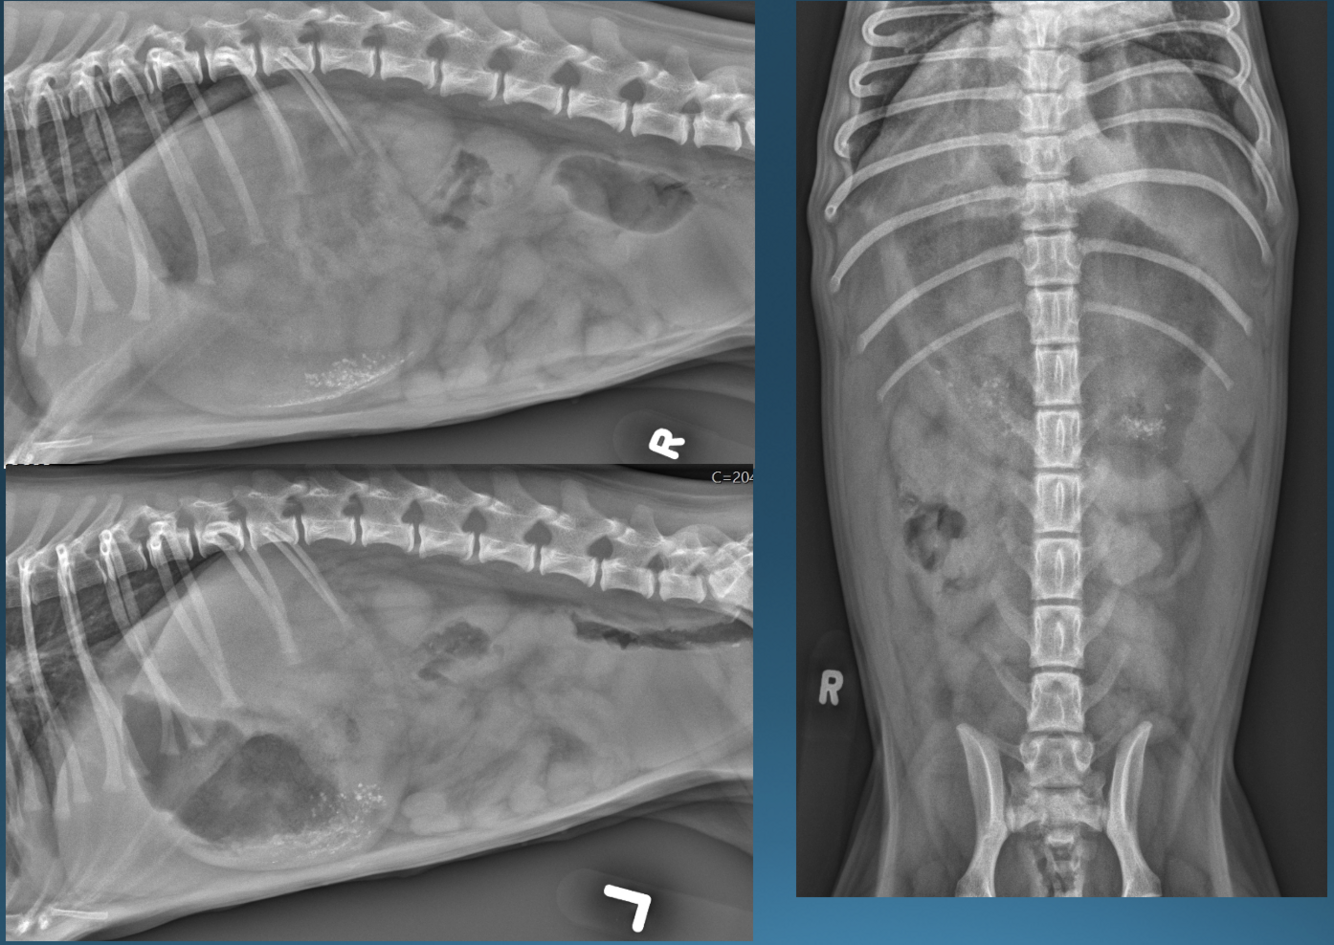

What is shown in this image?

A

hiatal hernia (feline)

What are the imaging findings in a hiatal hernia?

*caudal mediastinal structure in area of esophagus

-at margin of diaphragm

-soft tissue opacity +/- gas

*may appear continuous with the stomach

*may disappear if sliding